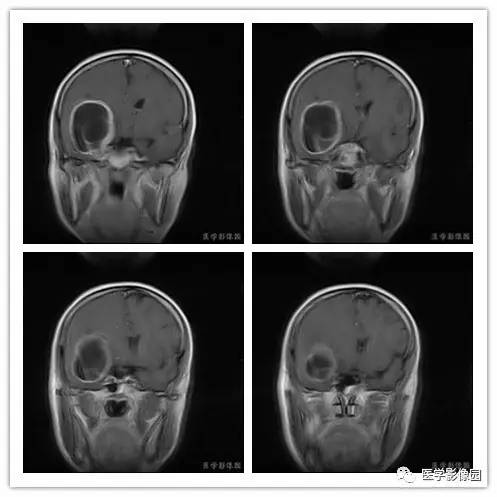

影像学表现:右侧颞叶深部区见一长T1、长T2囊样信号,成明显环形强化、未见明确结节影,没有FLAIR和DWI图,内见分隔,边界较清,周围水肿不明显,右侧脑室明显受压、颞角扩大,右侧脑沟明显变浅,脑中线结果向左偏移。

结果 血管外皮细胞瘤

血管外皮细胞瘤好发于颅底、矢状窦或大脑镰旁、小脑幕等硬脑膜或静脉窦附近。肿瘤多呈分叶形或不规则形,少数可呈椭圆形或扁圆形。多数具有脑外肿瘤特点,与脑膜或大脑镰和小脑幕有广基底连接,少数与脑膜以窄基底连接,后都可能是由于肿瘤生长时间短而又生长体积较大。

1.肿瘤主要表现为等长T1 、等长T2 混杂信号影,偶可见短T1 或短T2 信号影,注药后,肿瘤增强明显但不均匀;

2.外形呈不规则分叶状;

3.半数以上的肿瘤与硬膜窄基底相连;

4.肿瘤内常可见血管流空影而见不到钙化影;

5.肿瘤附近骨质可见破坏而见不到增生硬化。